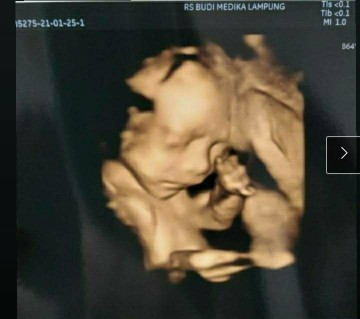

Bagus ga min ini baby aku d